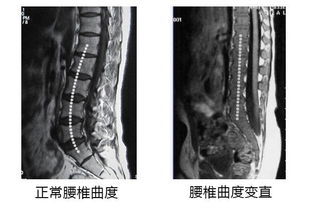

腰椎生理曲度变直,顾名思义,就是腰椎本来是向前有一个弧度的(见下图左图),现在变成了一根直棍(见下图右图),失去了正常的生理弧度。

大多数患者发现自己腰椎生理曲度变直是从影像检查报告单上发现的,如下图。